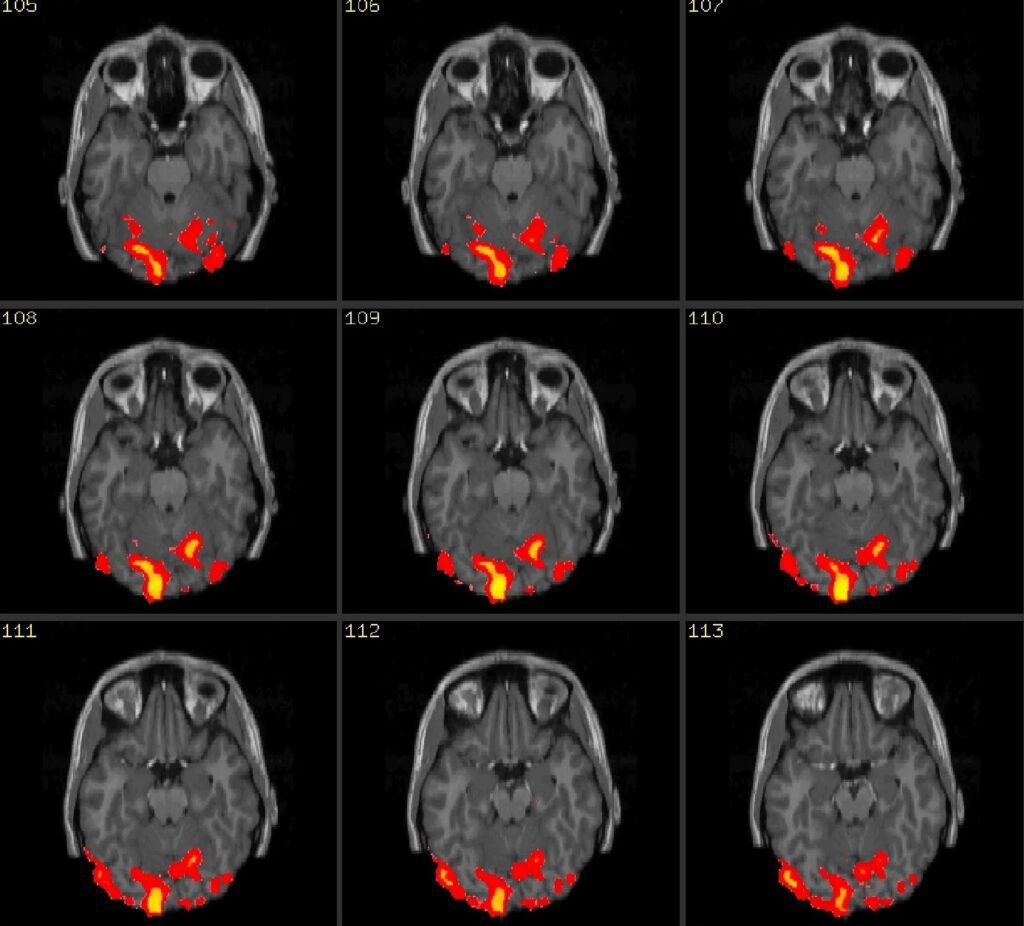

دیگر کاربرد هوش مصنوعی در روانشناسی، تصویربرداری از مغز است. الگوریتمهای یادگیری ماشین میتوانند دادههایی بزرگ حاصل از اسکن مغز را تجزیه و تحلیل کرده و الگوهای مناطق مختلف مغز را شناسایی کنند. محققان با کمک این اطلاعات میتوانند مفاهیمی همچون توجه، حافظه و تصمیمگیری را بهتر درک کرده و مکانیسم آنها را متوجه شوند.

- تصویربرداری عصبی: هوش مصنوعی به متخصصان این امکان را میدهد تا فعالیتهای عصبی را تشخیص داده و رابطه بین مناطق مختلف مغز و عملکرد آنها را بررسی کنند.